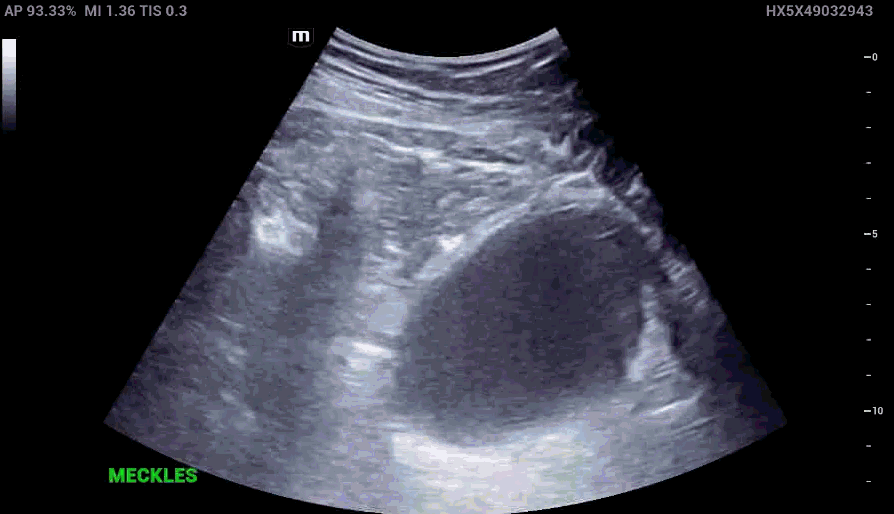

RLQ US:

Appendcitis was high on the differential with what looked like an appendocolith in the right lower quadrant with posterior acoustic shadowing. CT was ordered which showed the following:

The characteristic features of inflamed Meckel’s diverticulum can include the following findings:

• Fixed, blind ending tubular or cystic structure in the bowels.

• Thickened wall

• Irregular mucosal layer

• Tubular hyperechoic structure

• Surrounding hyperechoic fat representing pericolic inflammation

• May contain fluid, air or particulate material

• Hyperemia in the diverticular wall indicating inflammation

• Increased vascularity in the surrounding hyperechoic layer, which suggests perforation

• Small bowel obstruction may be present as a complication